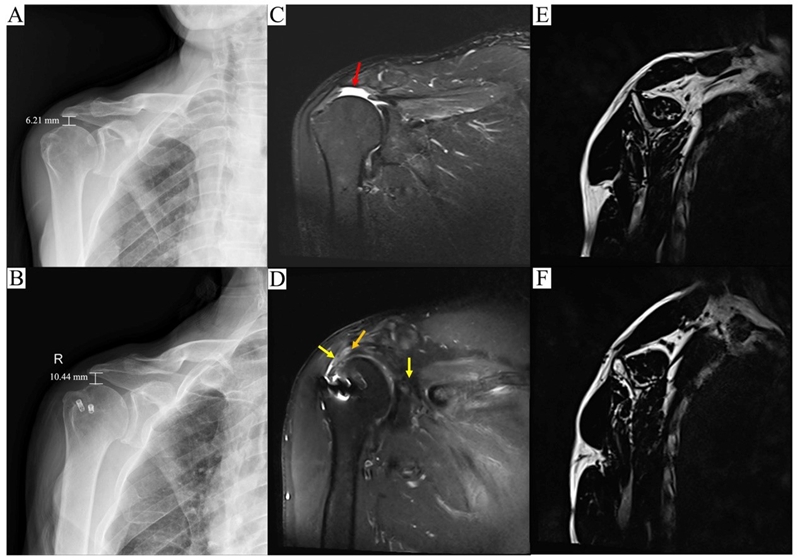

大鼠模型手术方式

与此同时,该研究团队对2019年-2022年所有进行上关节囊重建和动力化上关节囊重建的不可修复巨大肩袖撕裂患者进行临床随访,所有患者随访时间至少1年,从短期临床疗效上看,动力化上关节囊重建患者的肩关节活动度和肩关节功能改善更为明显;从MRI结果上看,冈上肌腱脂肪化程度得到明显改善。

MRI显示冈上肌腱脂肪化程度得到明显改善